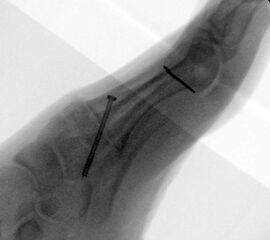

Es wird hier die Lapidusarthrodese mit Fixation durch eine medial angebrachte winkelstabile Platte in Kombination mit einer Zugschraube beschrieben 2. Durch diese Kombination läßt sich eine verglichen zur Schraubenosteosynthese hohe Primärstabilität erreichen, verbunden mit einem niedrigen Risiko einer Pseudarthrosenbildung 3.

Direkt postoperativ Röntgenkontrolle (Fuß in zwei Ebenen). Sechs Wochen postoperative Röntgenverlaufskontrolle in zwei Ebenen im Stehen. Ist die Überbauung der Arthrodese nicht gut zu beurteilen, kann eine ergänzende 45° Supinationsaufnahme des Fußes angefertigt werden, die einen guten Einblick in das Tarsometatarsale-I-Gelenk ermöglicht.